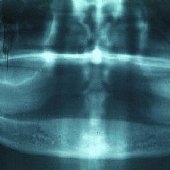

• Röntgenaufnahme eingesetzte Implantate mit aufgebrachten Durchtrittspfosten.

• Röntgendarstellung einer fest sitzenden Unterkieferbrücke mit 5 Implantaten.